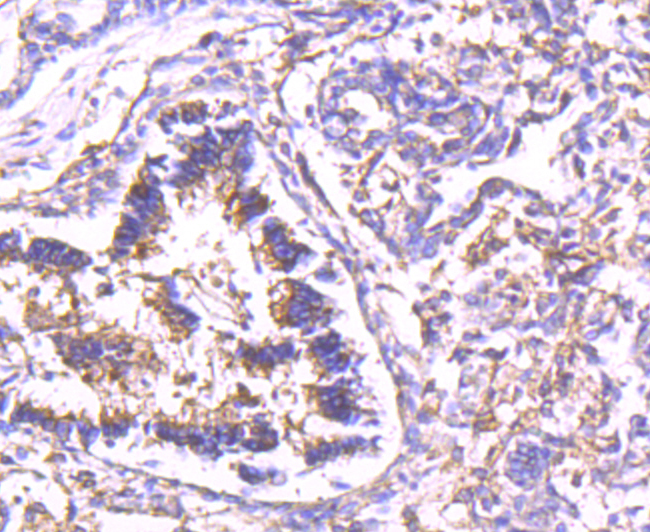

Immunohistochemical analysis of paraffin-embedded human lung tissue using anti-Calpain 2 antibody. Counter stained with hematoxylin.

Immunohistochemical analysis of paraffin-embedded human kidney tissue using anti-Calpain 2 antibody. Counter stained with hematoxylin.